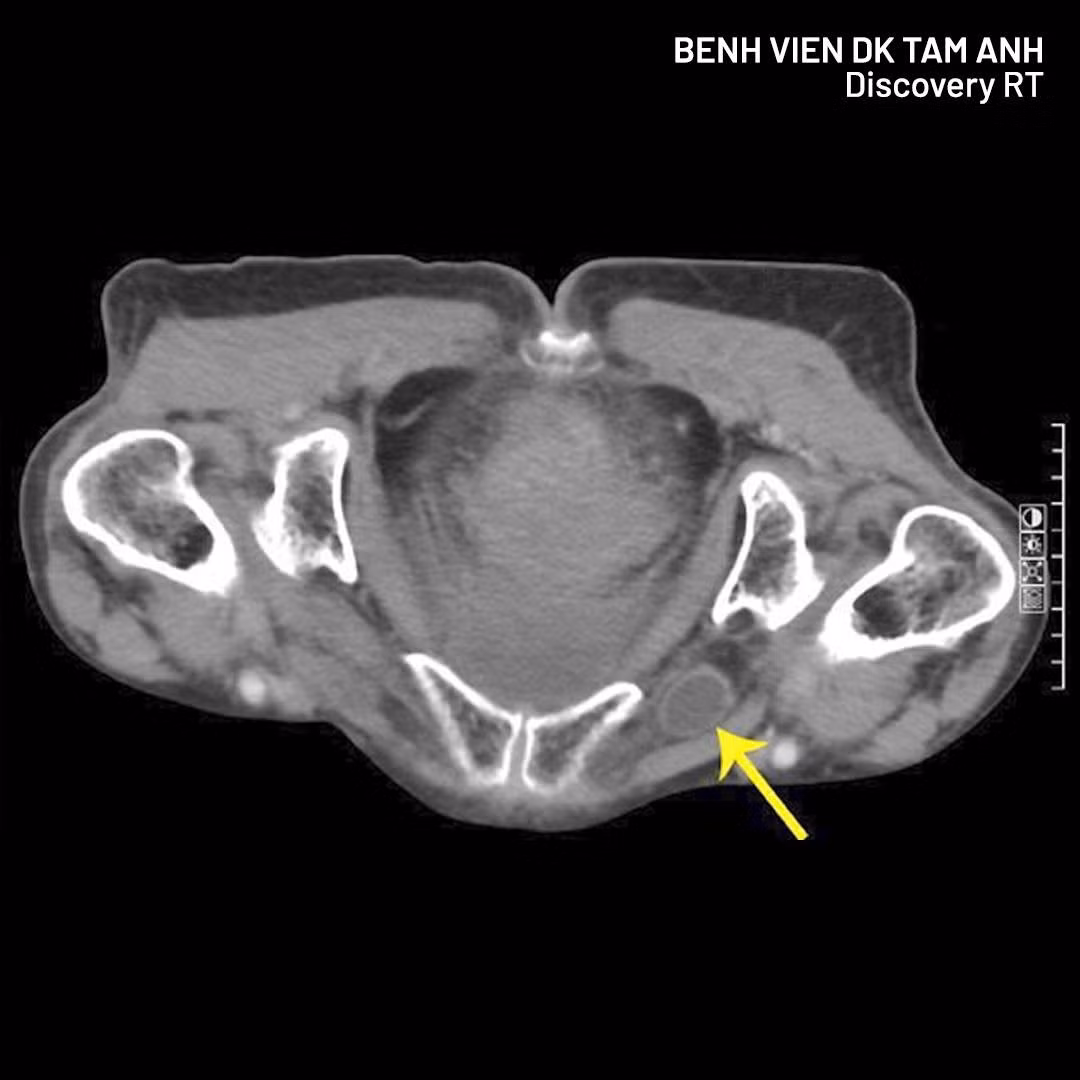

Hình ảnh thoát vị qua CT - Ảnh BVCC

Qua hình chụp CT, phát hiện quai ruột non chui qua lỗ bịt gây tắc ruột. Nếu chậm trễ, nguy cơ hoại tử ruột, thủng ruột và đe dọa tính mạng rất cao. Nhờ thăm khám kỹ lưỡng kết hợp chẩn đoán hình ảnh hiện đại, nguyên nhân nguy hiểm đã được phát hiện kịp thời, giúp người bệnh tránh biến chứng nặng.

Trước tình trạng của bà Thoa, ê-kíp nhanh chóng lựa chọn phẫu thuật nội soi cấp cứu. Hình ảnh CT cho thấy quai ruột chưa hoại tử, tạo điều kiện can thiệp kịp thời, tránh phải mổ mở và cắt ruột nhiều rủi ro.